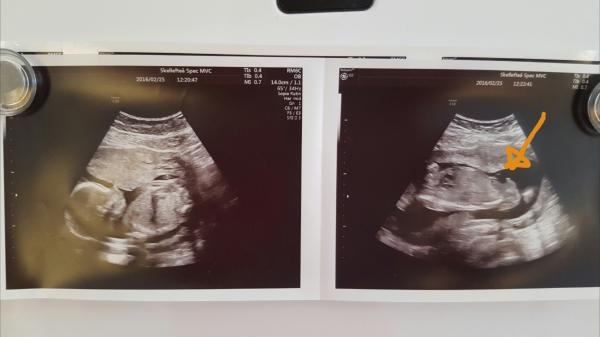

Kön ?? Nån som ser?

Nån som ser... och har ev nån liknande bild?

En pojke?

Jag vet inte... är förvirrad... det där ultraljudet gjorde v 19-20 .. och jag utbrast åååå en pojke och läkaren höll med..

Varit på ett annat idag och bebis var inte sammarbetsvillig. . Men hon kunde inte se att det skulle vara en pojke..

Ser väldigt pojkigt ut med pung och snopp:)

Någon snäll själ här som har lust att gissa kön? Jag är så nyfiken!! :) Vecka 14+1. Tack på förhand! :)